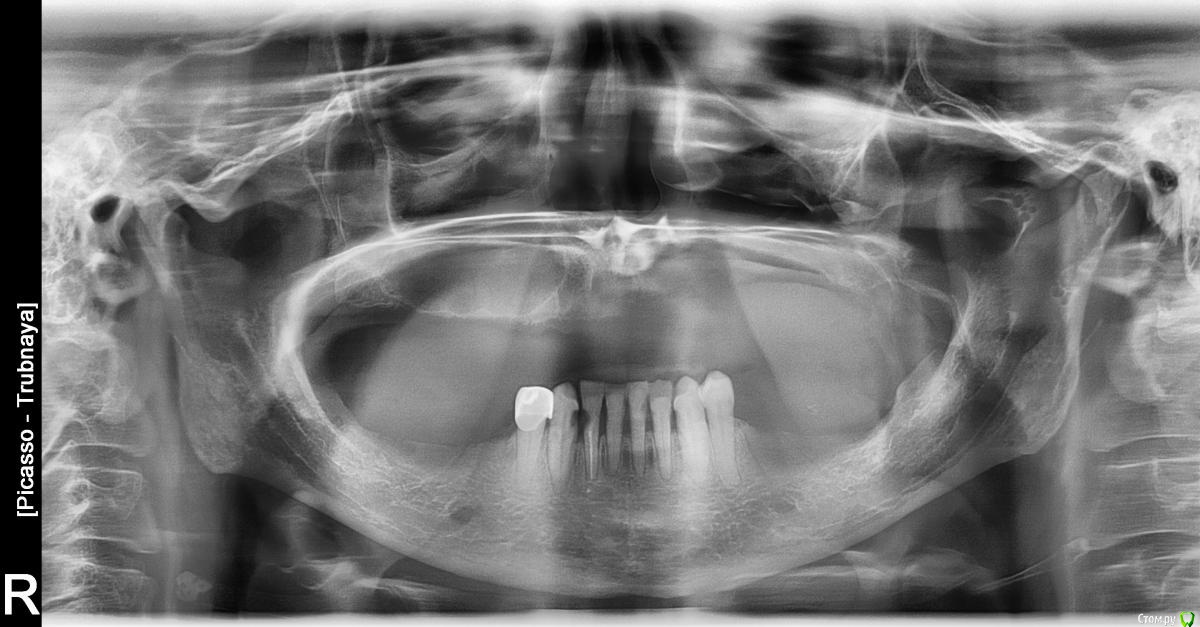

Всем добрый день! Ищу врача и всем заранее благодарна за неравнодушие. Было много операций, но проблема как бы остается в стороне, где-то между дном носа и пазухой, нет дренажа, чувствую патологическую полость, где собирается патологическое содержимое , у которого нет выхода.

Внешне здоровые зубы - 21-27 были удалены по настоянию, и каждый из них имел целую эпопею. У 25 провалилась пломба, сразу после пломбирования, после удаления 24 прекратился гной сразу, у 22 тоже сразу провалилась пломба после пломбирования, у 21 после удаления образовался свищ, 23- после пломбирования боль стала невыносимой, удалили, якобы в этой области был секвестр. Рекомендовали альвеэктомию, но никто не взялся. Мучаюсь уже 10 лет. На дне носа был долго свищ, из которого периодически вытекал гной. Свищ вычистили, закрылся, стало хуже. Секвестр? Назолябильная киста?

Прошу всех подскажите , неужели нет вариантов? Постоянно на антибиотиках, 10 лет ( перерывы 2-3 дня).